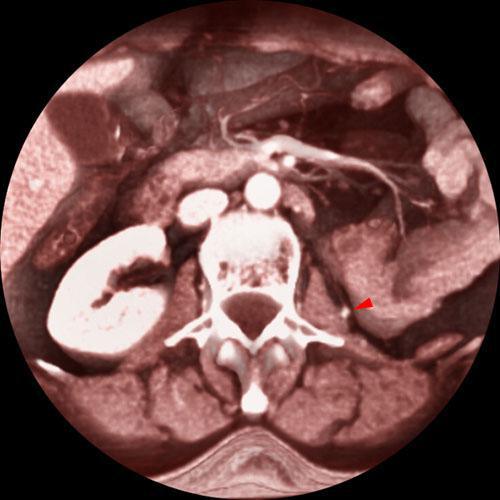

Nefrectomía parcial. Tumorectomia